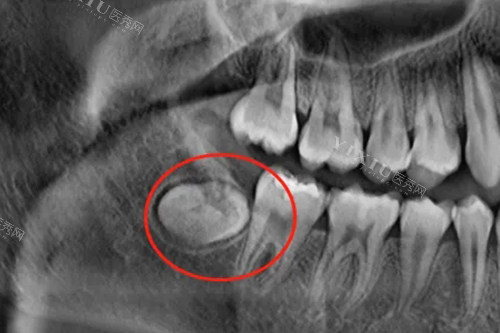

然而,如果智齿长得位置不佳,导致拥挤、疼痛或感染等问题,那么拔掉智齿可能会是更好的选择。拔掉智齿可以避免潜在的长期问题,如智齿囊肿、牙周炎等。另外,拔掉智齿还可以防止未来出现智齿移位、牙齿错合等问题。

在做出决定之前,建议询问资质完善的牙医的建议。医生会通过X光检查和口腔检查来评估智齿的具体情况,并给出相应的治疗建议。有时候,智齿问题不仅仅是个人口腔健康问题,还可能涉及到整体身体健康。